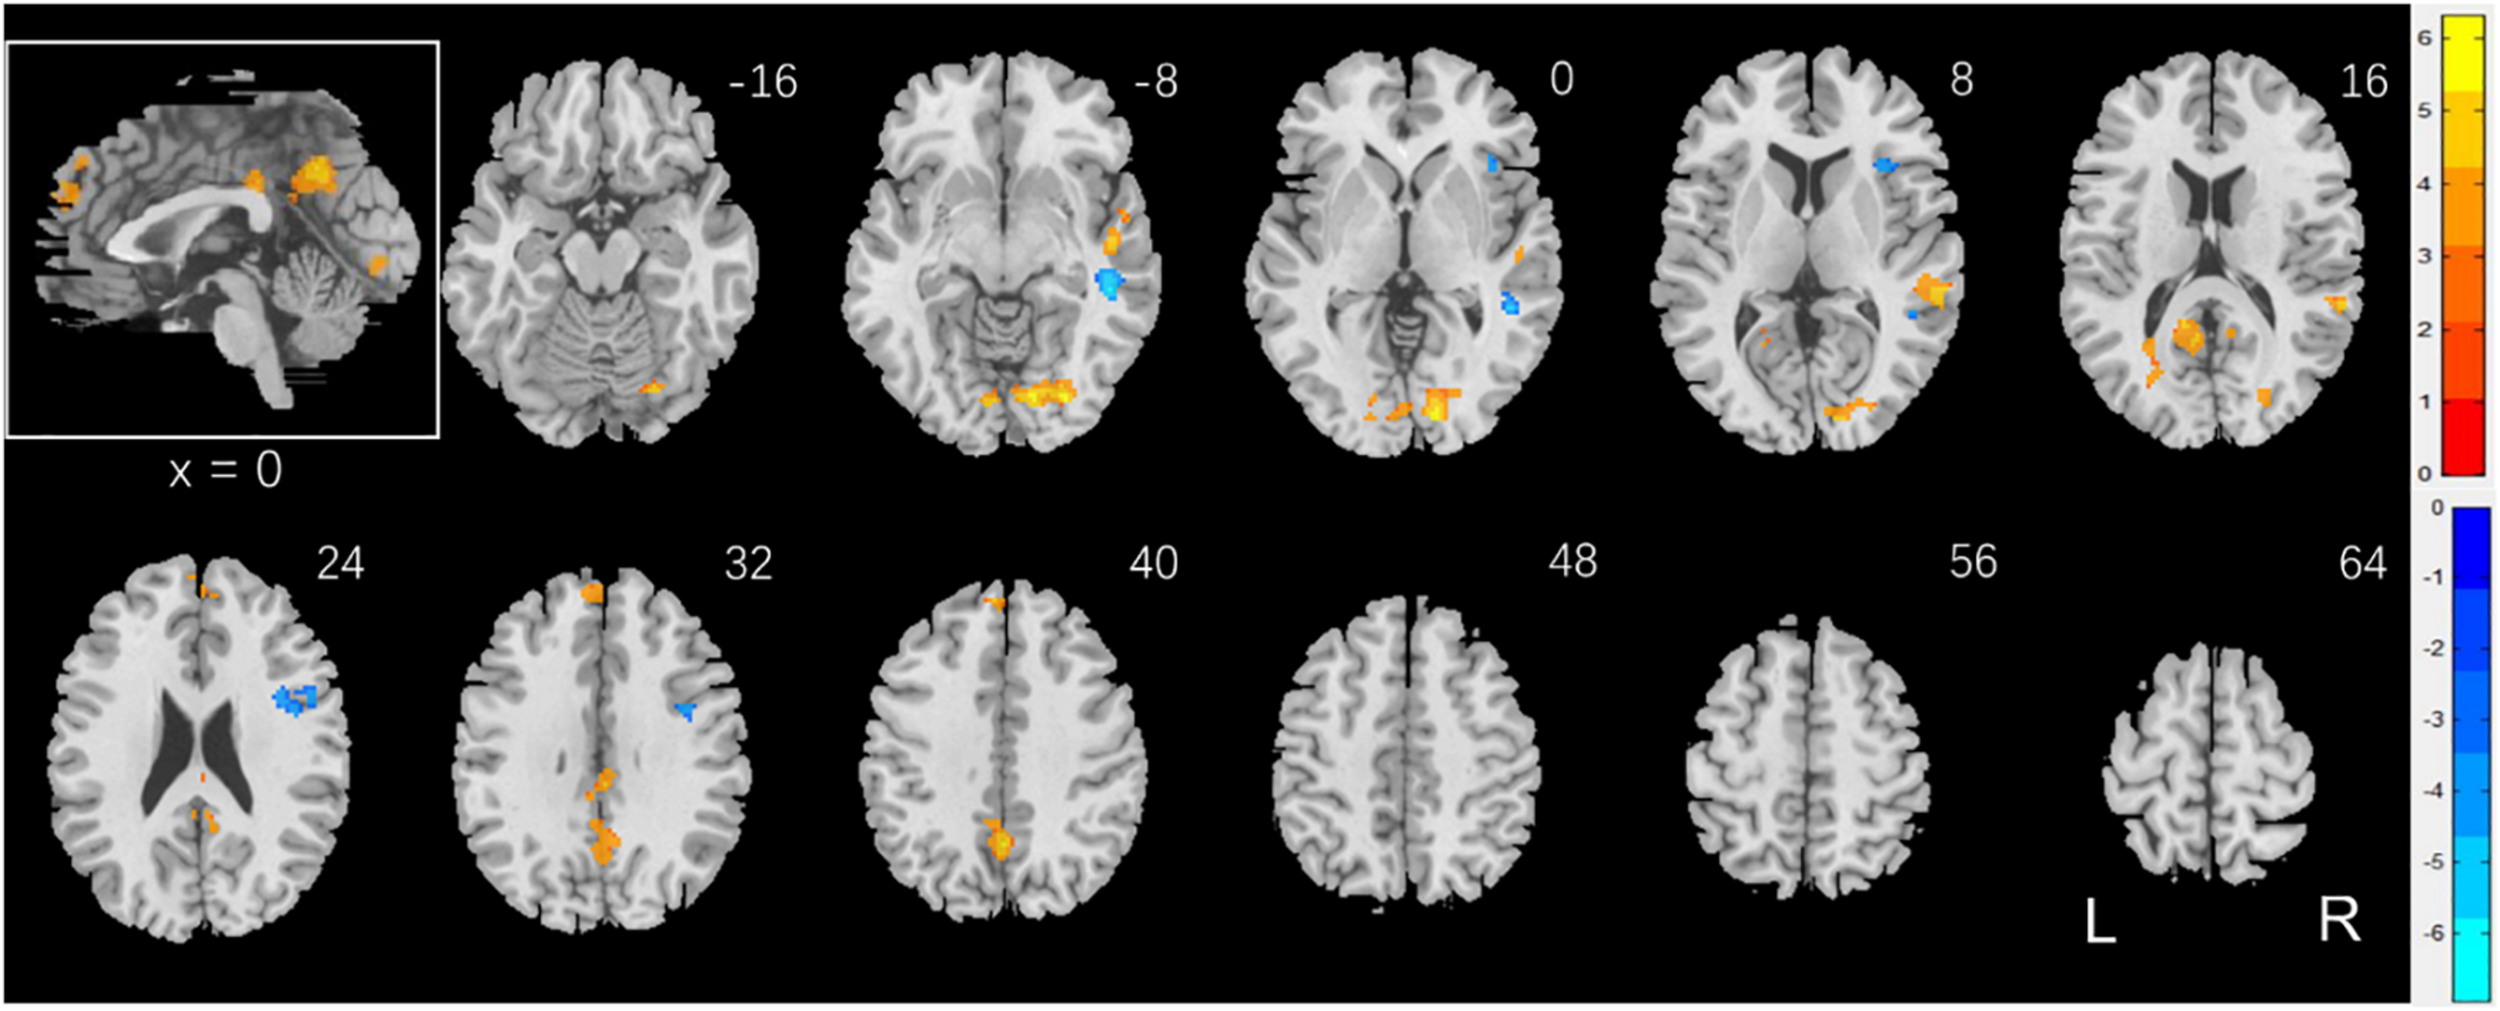

Brain Activations to Social vs. Random Stimuli in Correlation With Accuracy Rate

Individuals varied in how accurately they identified social vs. random interactions. We conducted a whole brain linear regression of the contrast (social vs. random) against “ARSOC – ARRAN” across all subjects, with sex, age, and years of education as covariates. Clusters that met the threshold of voxel p < 0.001, uncorrected, in combination with cluster p < 0.05 FWE-corrected are shown in Figure 3A. A cluster in the paracentral lobule (PCL) showed activation in positive correlation with ARSOC – ARRAN. Bilateral anterior insula (AI), dorsomedial prefrontal cortex in the anterior pre-supplementary motor area (preSMA), and the left middle frontal gyrus (MFG) showed higher activation to social vs. random interaction in negative correlation with ARSOC – ARRAN.

FIGURE 3

www.frontiersin.org

Figure 3. Regional responses to social interaction vs. random movement in correlation with “ARSOC – ARRAN” in (A) all subjects: whole-brain regression with sex, age, and years of education as covariates; and in (B) men and (C) women separately, with age and years of education as covariates. Warm/cool color bars show clusters with positive/negative correlation with “ARSOC – ARRAN”; p < 0.001, uncorrected, in combination with cluster p < 0.05 FWE-corrected. The insets highlight the clusters in a mid-sagittal section.

We next conducted a whole brain linear regression of contrast (social – random) against “ARSOC – ARRAN” for men and women separately, with age and years of education as covariates. For men alone, no clusters showed activation in positive correlation with “ARSOC – ARRAN.” Bilateral AI, anterior preSMA, left MFG and inferior superior frontal gyrus showed activation in negative correlation with “ARSOC – ARRAN” (Figure 3B). For women alone, a cluster each in the precuneus and in the medial orbitofrontal cortex showed activation in positive correlation with “ARSOC – ARRAN” (Figure 3C). No clusters showed activations in negative correlation. These clusters are summarized in Table 3.

Table 3. Regional activations in correlation with ARSOC – ARRAN.